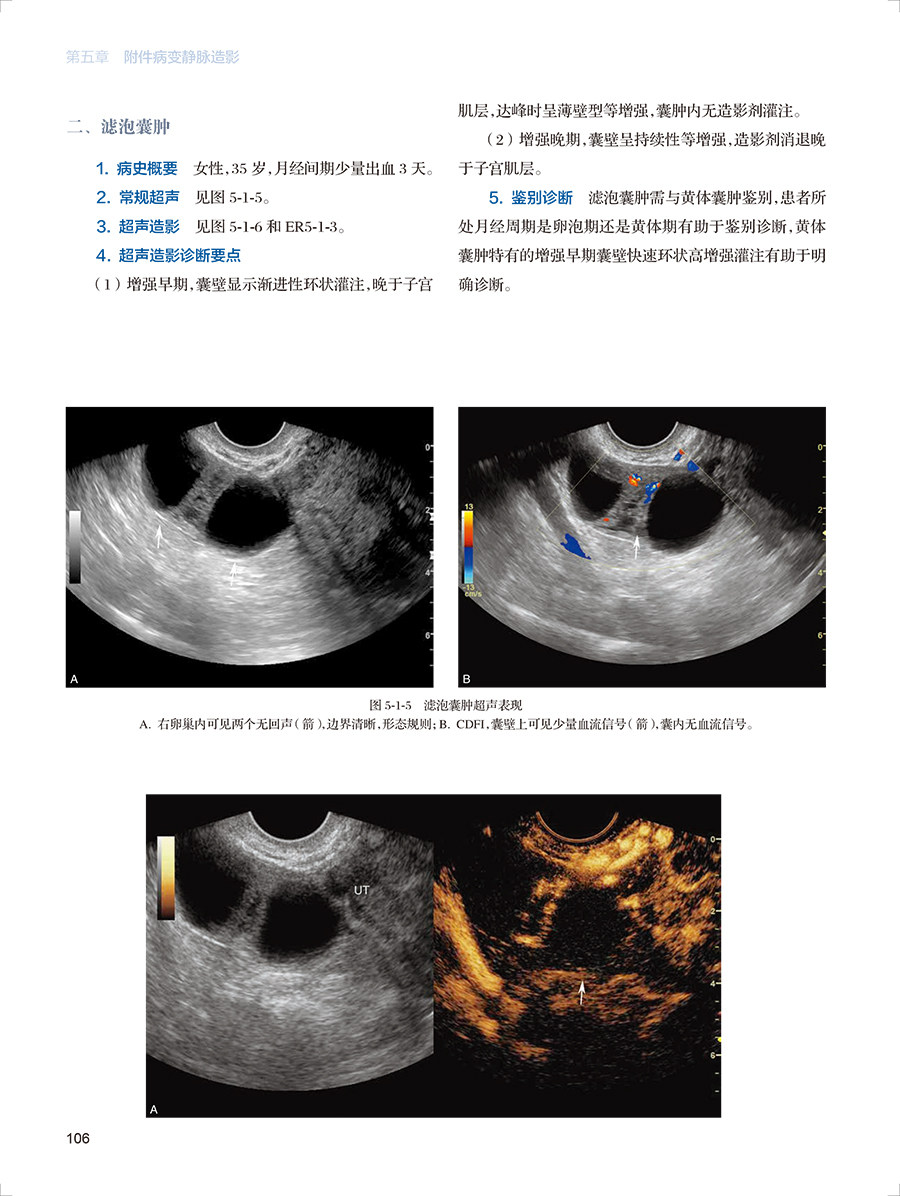

二、滤泡囊肿